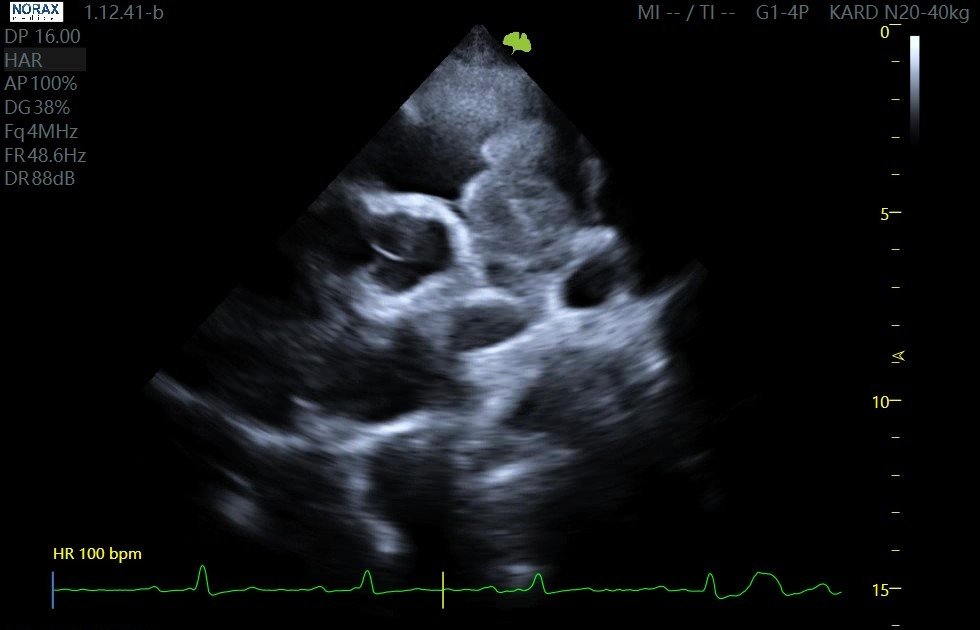

Fenotypowa kardiomiopatia restrykcyjna (RCM) u kota

Przypadek pacjenta lek.wet. Magdaleny Domańskiej z lecznicy Vet-Kart w Kartuzach. Aparat: VINNO R700 VET. Przedstawiony pacjent to 14-letni kot, mieszaniec, u którego rozpoznano fenotypową kardiomiopatię restrykcyjną. Pierwsze badanie echokardiograficzne: powiększony lewy przedsionek, znacznie osłabiona kurczliwość lewego przedsionka (pomiar LAFS – frakcja skracania lewego przedsionka) oraz masywny spontaniczny echokontrast (SEC). Drugie badanie – po trzech miesiącach […]